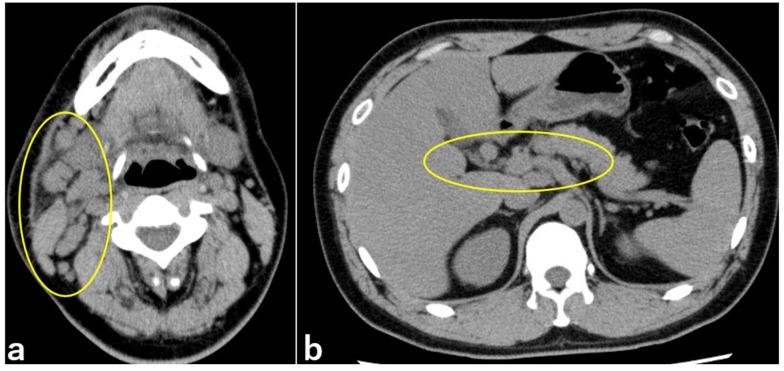

: Parinaud oculoglandular syndrome (POS) is unilateral granulomatous follicular conjunctivitis with ipsilateral afferent lymphadenopathy, primarily caused by cat-scratch disease, tularemia, and sporotrichosis. We report a case of POS in which DNA was detected using polymerase chain reaction (PCR) in corneal and conjunctival specimens. : A 29-year-old man, who started keeping a stray cat two months prior, became aware of right preauricular lymphadenopathy and right ocular conjunctival hyperemia one month prior. Subsequently, he developed a fever of approximately 37.9 °C, with a purulent ocular discharge appearing 1 week before being referred to our department for a detailed ophthalmological examination. The patient's right eye showed hyperemia and edema in the bulbar conjunctiva, along with palpebral conjunctival hyperemia, follicles, and white ulcers. Two weeks later, his serum IgM titer for was 1:20, and DNA was detected by PCR in the corneal and conjunctival specimens. Based on these findings, the patient was diagnosed with POS caused by cat-scratch disease (CSD). Oral doxycycline, rifampicin, topical gatifloxacin, betamethasone phosphate, and erythromycin eye ointments were prescribed. : After 2 weeks of oral treatment and 2 months of eye drop treatment, the deterioration of the cornea and conjunctiva improved when the patient recovered good visual acuity. : PCR assays of corneal and conjunctival specimens are useful for the diagnosis of CSD presenting with POS. These results suggested that may be directly involved in the ocular surface pathogenesis of POS.

一名 29 岁男子,两个月前开始收养一只流浪猫,一个月前发现右耳前淋巴结肿大和右眼结膜充血。随后,他出现约 37.9°C 的发热,1 周前出现脓性眼分泌物,随后到我院进行详细眼科检查。患者右眼球结膜充血水肿,伴有睑结膜充血、滤泡和白色溃疡。两周后,其血清 IgM 滴度为 1:20,PCR 检测到角膜和结膜标本中的 DNA。根据这些发现,患者被诊断为猫抓病(CSD)引起的 POS。给予口服多西环素、利福平、局部加替沙星、磷酸倍他米松和红霉素眼膏。